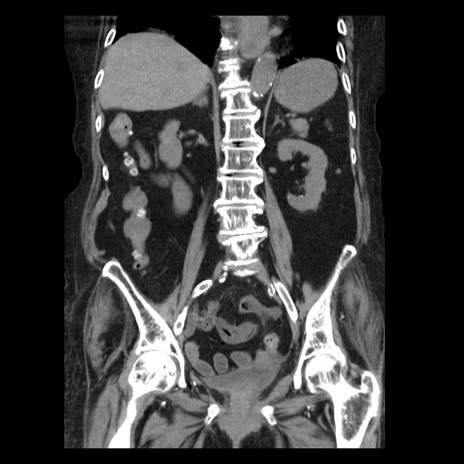

症例14(冠状断像)

【症例】 90歳代女性

【主訴】 腹痛・嘔吐

【現病歴】今朝から左側腹部痛を認めた。 経過観察していたが、嘔吐を認めたため来院。

【既往歴】 子宮癌術後

【身体所見】 意識清明、BP 127/54mmHg、P 98bpm Sp02 95%(RA)、BT 35.8°C、腹部平坦・軟腸ぜん動音聴取良好、右下腹部圧痛(+) 反跳痛なし

【データ】WBC 9800、CRP 0.46